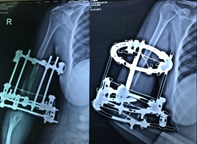

Case-III

62 years, female;

Broken IMN of fracture tibia and fibula (Implant failure) (Figure 11-13).

Figure 11 X-ray broken IM nail after fall.

Figure 12 Post-operative x-ray after Ilizarov operation.

Figure 13 X-ray after union.